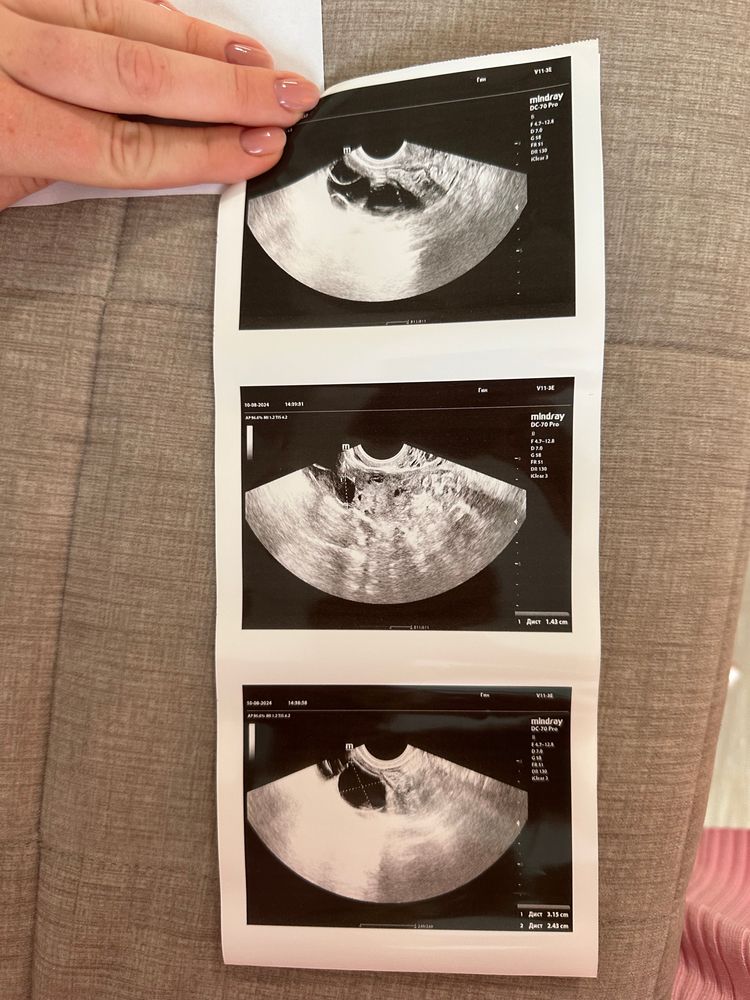

Беременность после неудачных форум 87 фото